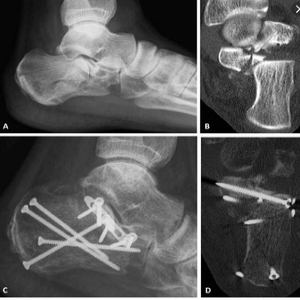

We Provide Best foot and ankle doctor in Nagpur